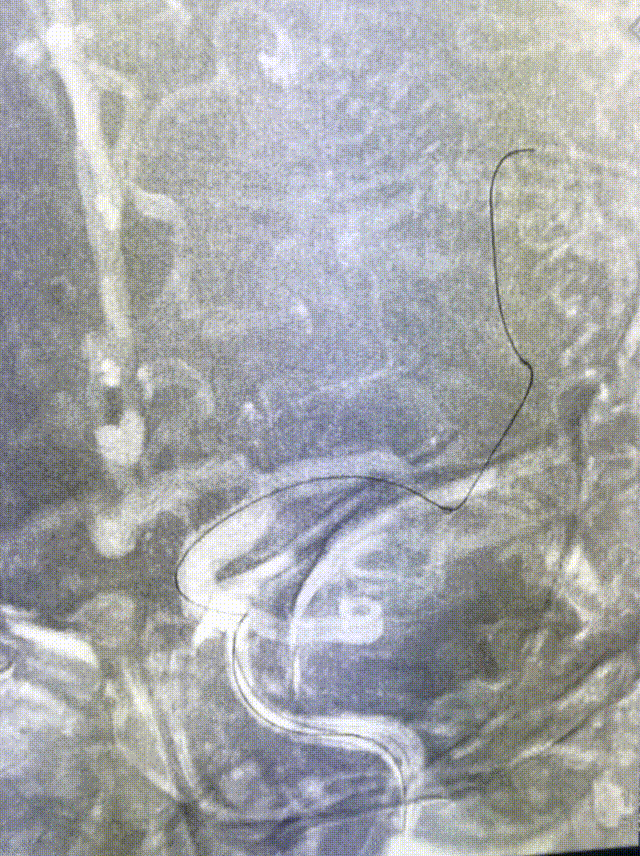

CTA示左侧大脑中动脉闭塞。

造影证实左侧大脑中动脉M1段闭塞。

构建治疗通路,微导管穿过闭塞段后造影确认真腔,置入Syphonet®取栓支架,支架通体显影,提供良好的视觉反馈,全程可视化操作。